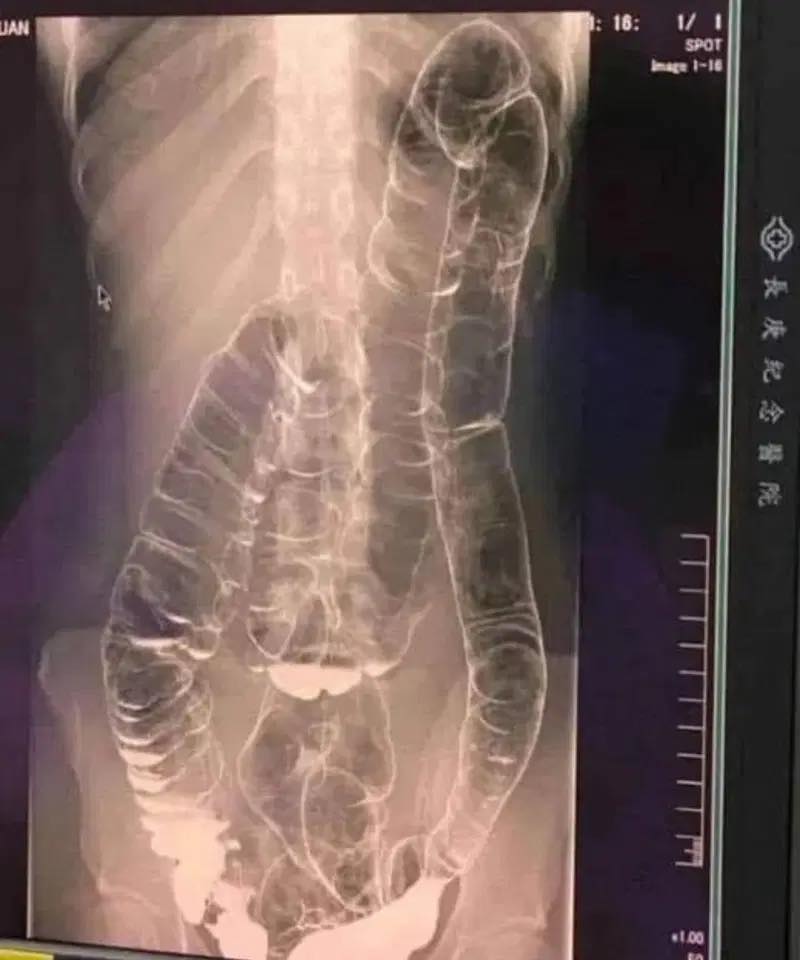

Who hasn’t encountered constipation? This problem, often perceived as trivial, can transform into a real nightmare if it becomes constant. This is exactly what occured to a young woman whose overloaded colon ended up dangerously dilating. So, how can we prevent this digestive disorder from taking a noticeble turn?

A saturated colon

When you don’t have regular bowel movements, waste builds up in the colon. The result: extra pressure that can cause pain, bloating , and, in severe cases, terrible complications.

- Colon distension: Over time, the colon weakens its elasticity and becomes increasingly difficult to remove stools.

- Bowel obstruction: In extreme cases, fecal matter can completely block the intestine, demanding emergency surgery .